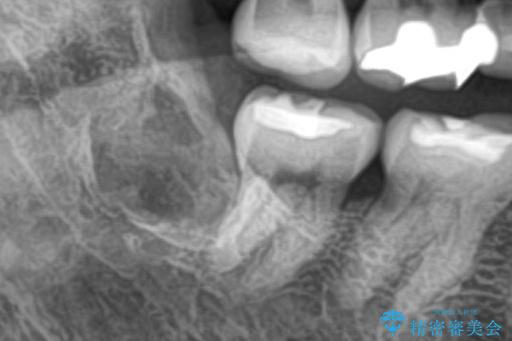

埋伏歯の抜歯

埋まっている親知らずを抜歯したいとご来院されました。

治療計画

パノラマ,CT撮影を行い安全なことを確認して抜歯を行いました。